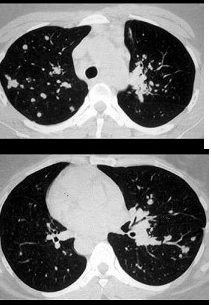

男,64岁,咳嗽半月,咯血1天,不发热,结合图像,最可能的诊断是( )

A:金葡菌肺炎

B:肺转移瘤

C:肺结核

D:结节病

E:组织胞浆菌病